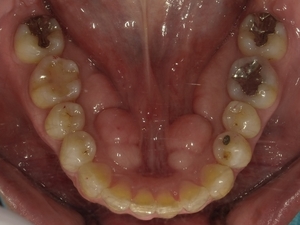

○ご相談内容:下の歯のがたつき○矯正の種類:マウスピース型矯正「クリアコレクト」○治療期間:10週間○治療費用:66万円(税込)